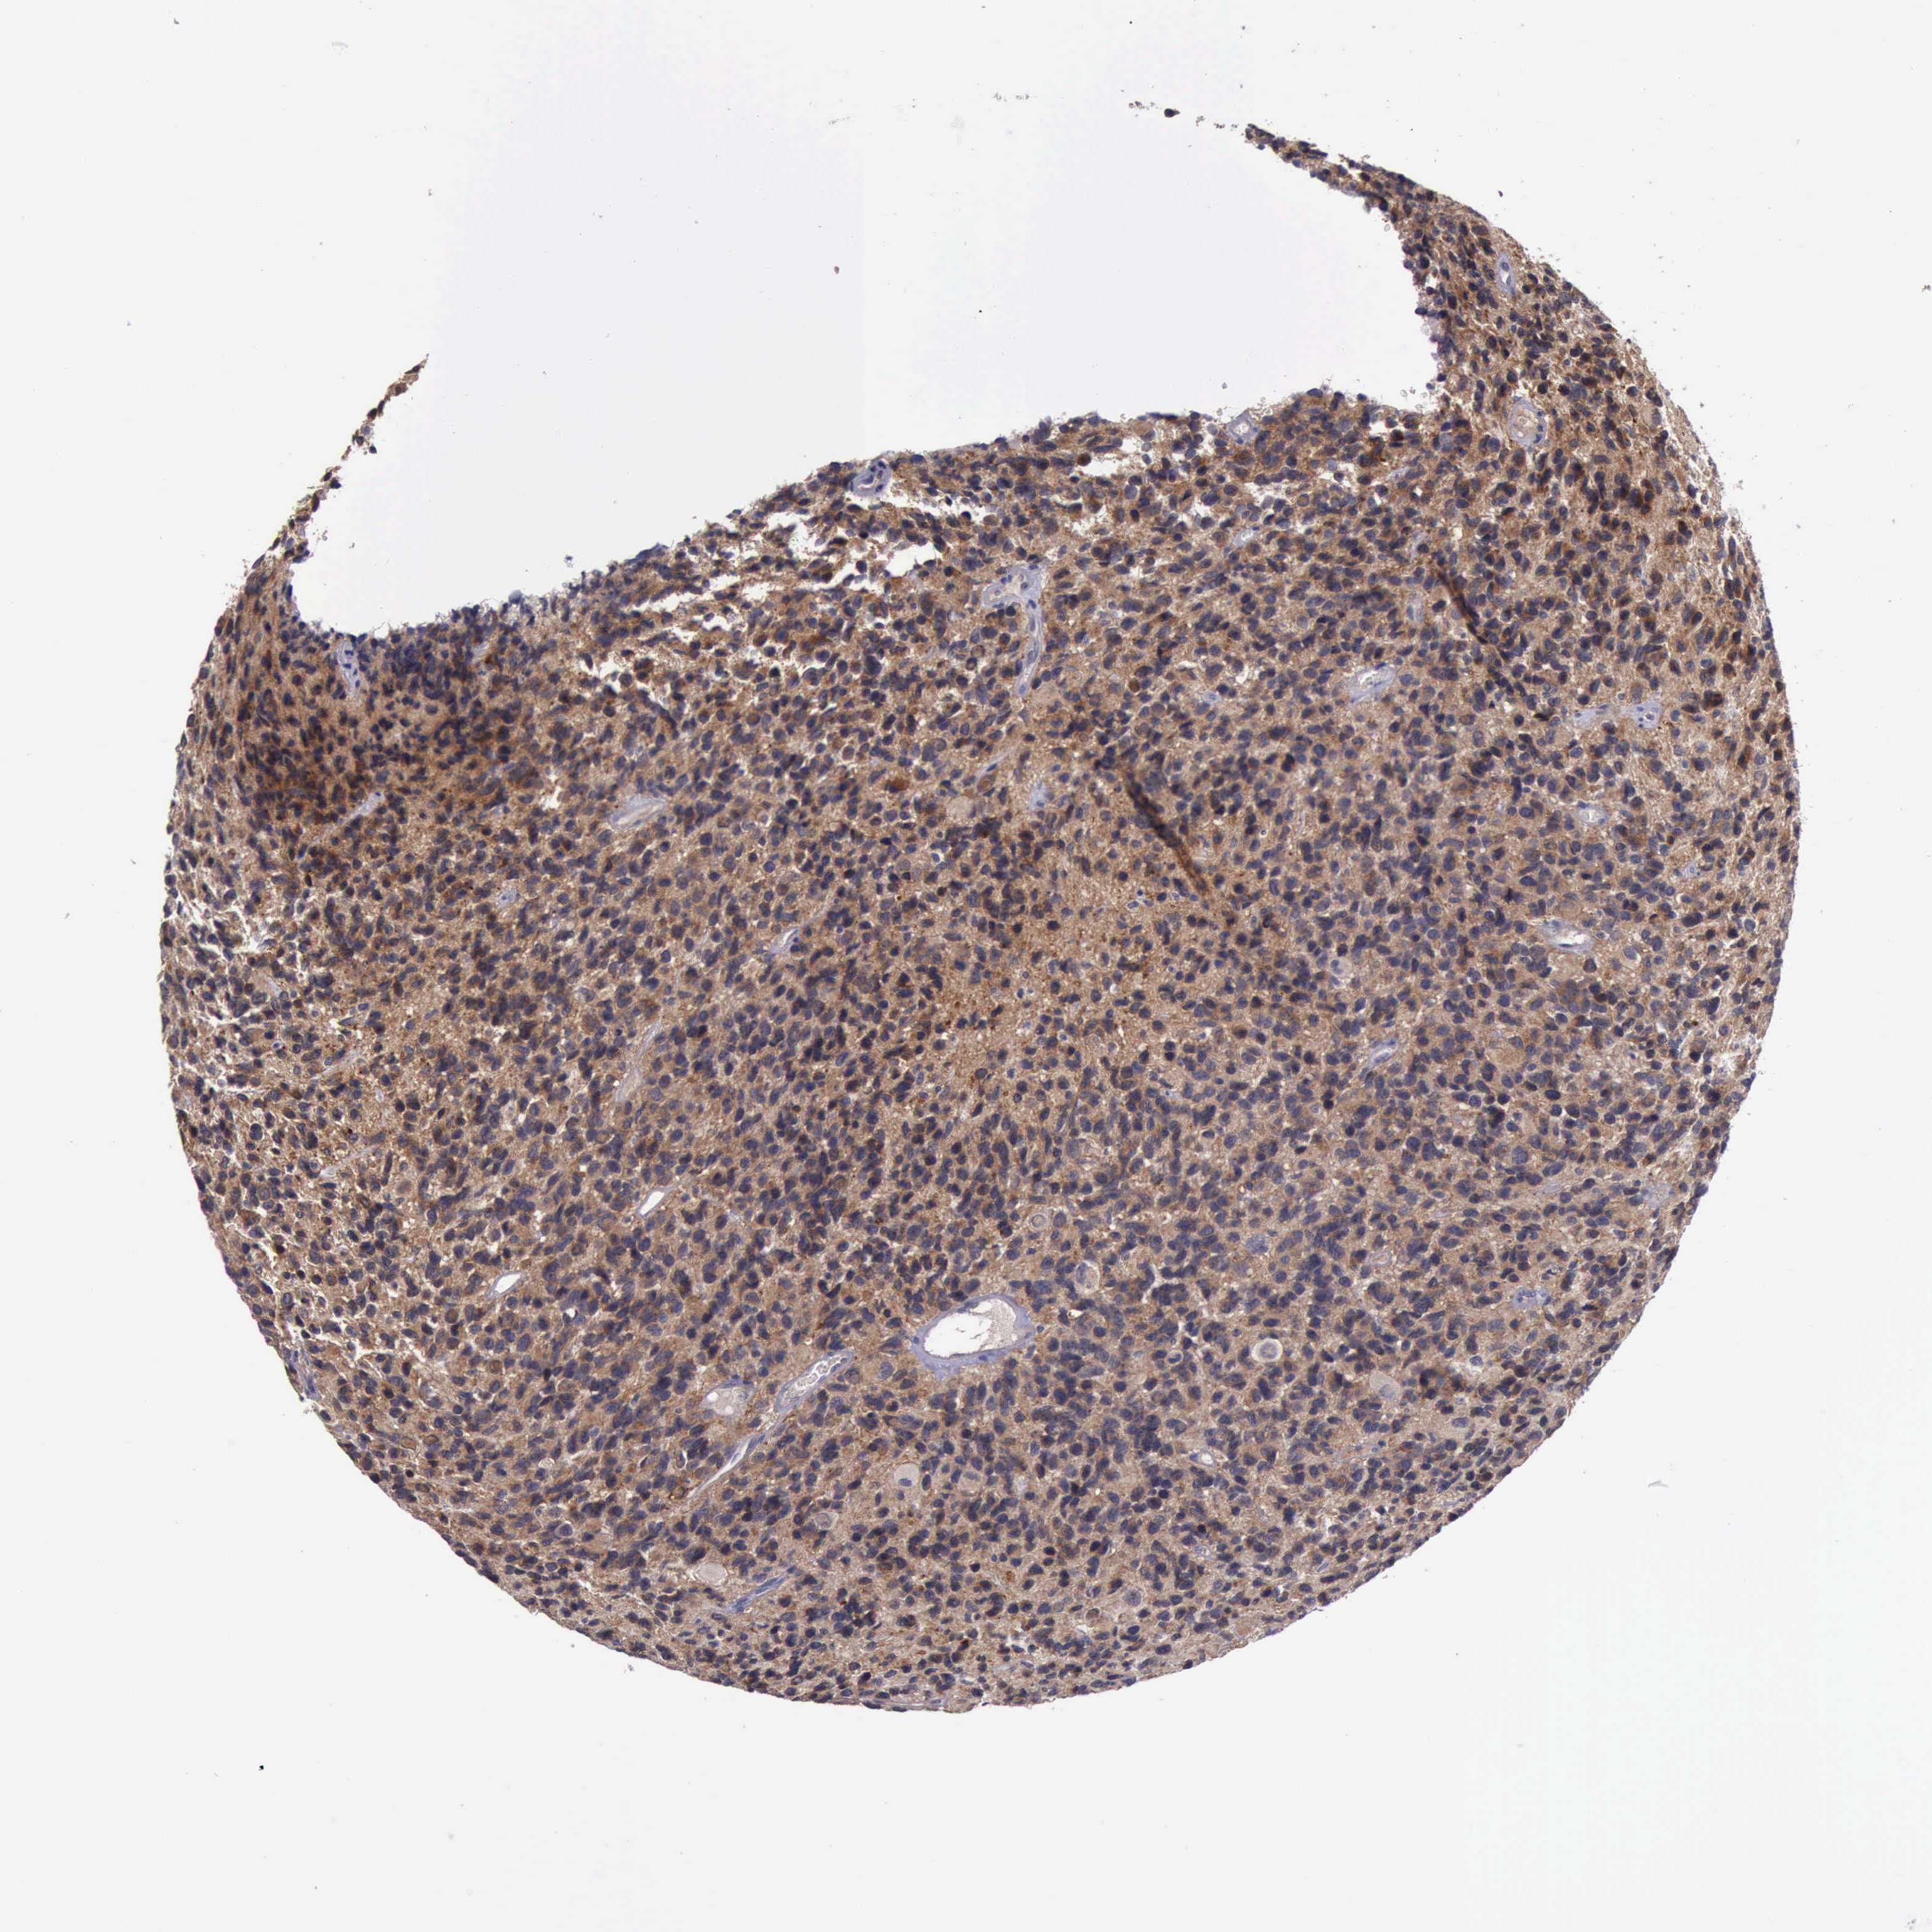

GLIOMA - Protein expressioni

A mouse-over function shows sample information and annotation data. Click on an image to view it in a full screen mode. Samples can be filtered based on level of antibody staining by selecting one or several of the following categories: high, medium, low and not detected. The assay and annotation is described here.

Note that samples used for immunohistochemistry by the Human Protein Atlas do not correspond to samples in the TCGA dataset.

Antibody stainingi

Antibody staining in the annotated cell types in the current human tissue is reported as not detected, low, medium, or high, based on conventional immunohistochemistry profiling in selected tissues. This score is based on the combination of the staining intensity and fraction of stained cells.

Each image is clickable and will lead to virtual microscopy that enables deeper exploration of all samples and also displays staining intensity scores, fraction scores and subcellular localization as well as patient and tissue information for each sample.

Antibody HPA001114

Antibody HPA042505

Staining

High

Medium

Low

Not detected

Intensity

Strong

Moderate

Weak

Negative

Quantity

>75%

75%-25%

<25%

None

Location

Nuclear

Cytoplasmic/membranous

Cytoplasmic/membranous,nuclear

Glioma, malignant, High grade

Glioma, malignant, Low grade